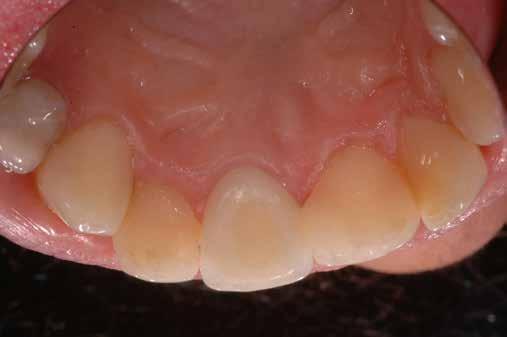

A korai harmicas éveiben járó hölgy rendelőnkbe érkezésének oka a jobb felső nagymetsző fog bizonytalan érzkenysége, elmondása alapján gyermekkorában trauma érte a felső frontrégiót. A frakturált klinikai koronákat kompozittöméssel helyreállították, egyéb kezelést akkor nem tartottak szükségesnek. Az utóbbi hónapokban tapasztalt érzékenység miatt kereste fel rendelőnket. A klinikai vizsgálat (1. és 2. kép) és a CBCT felvétel (3. kép) alapján diagnosztizált külső gyökérreszorpció megoldására a fog eltávolítását, implantátum

behelyezését, majd csavarozott rögzítésű, cirkónium-dioxid vázas, kerámialeplezésű korona készítését terveztük [1., 5., 6., 8.].

bukkális 1. kép: Kiindulási állapot, 2020. január. 3. kép: Kiindulási CBCT felvétel. 2. kép: Kiindulási állapot a palatinális oldal felől.

A 2020 januárjában elkezdett kezeléssorozat befejezését az év márciusában, hazánkba is begyűrűző Covid-19 pandémia késleltette, így kb. 6 hónap gyógyulás után láttunk hozzá az emergencia profil és a gingivális zenit ideiglenes koronával történő formázásához (11. és 12. kép). A 3 hetente végzett apró alakításokkal sikerült megfelelő ínyprofilt kialakítani, a „rózsaszín esztétika” a páciens számára is megfelelő volt. A bal felső nagymetsző fog meziális kompozit tömés cseréjét követően, individualizált nyitott kanalas lenyomati fejet készítettünk: az akrilát ideiglenes korona profilját átlátszó szilikonnal lemásoltuk, majd a körszimmetrikus gyári lenyomati fej és az ideiglenes korona kontúrja közötti hézagot folyékony kompozittal töltöttük ki (13. kép). Az így készített egyéni lenyomati fejjel vettünk lenyomatot a végleges, kerámialeplezésű cirkónium-dioxid vázas, átmenő csavaros rögzítésű koronához. (A fogtechnikai munkát Nébl Péter fogtechnikusmester készítette.), (14., 15., 16 és 17. képek).

A kész korona átadásakor a páciens elégedett volt az esztétikával, az azóta eltelt évben rendszeres kontrollokon jelent meg, melyek során meggyőződtünk a kemény- és lágyszövetek stabilitásáról (18. és 19. képek).

17. a–b képek: A kész munka átadáskor. 18. a–c képek: 1 éves kontroll. 19. kép: Intraorális kontroll röntgen felvétele 1 évvel az átadás után.